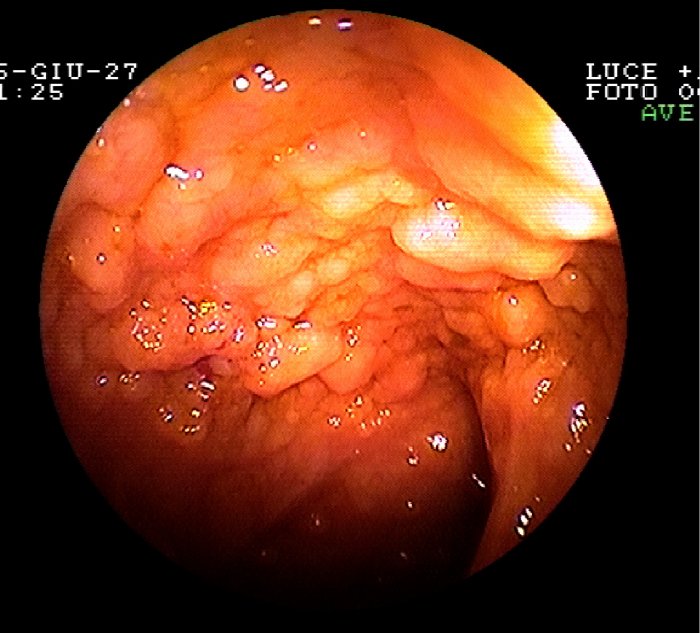

L'ultima ansa ileale

mostrava grossolane granularità ad aspetto ipertrofico, simili

a mammellonature discretamente fragili (Figura

1); buona austratura e plasticità di tutto il colon;

assenza di lesioni ulcero-erosive. L'esame istologico ha confermato

Figura 1. Mucosa ileale con presenza di grossolane granularità ad aspetto ipertrofico della mucosa, simili a mammellonature discretamente fragili. Assenza di lesioni ulcero-erosive e di iperemia